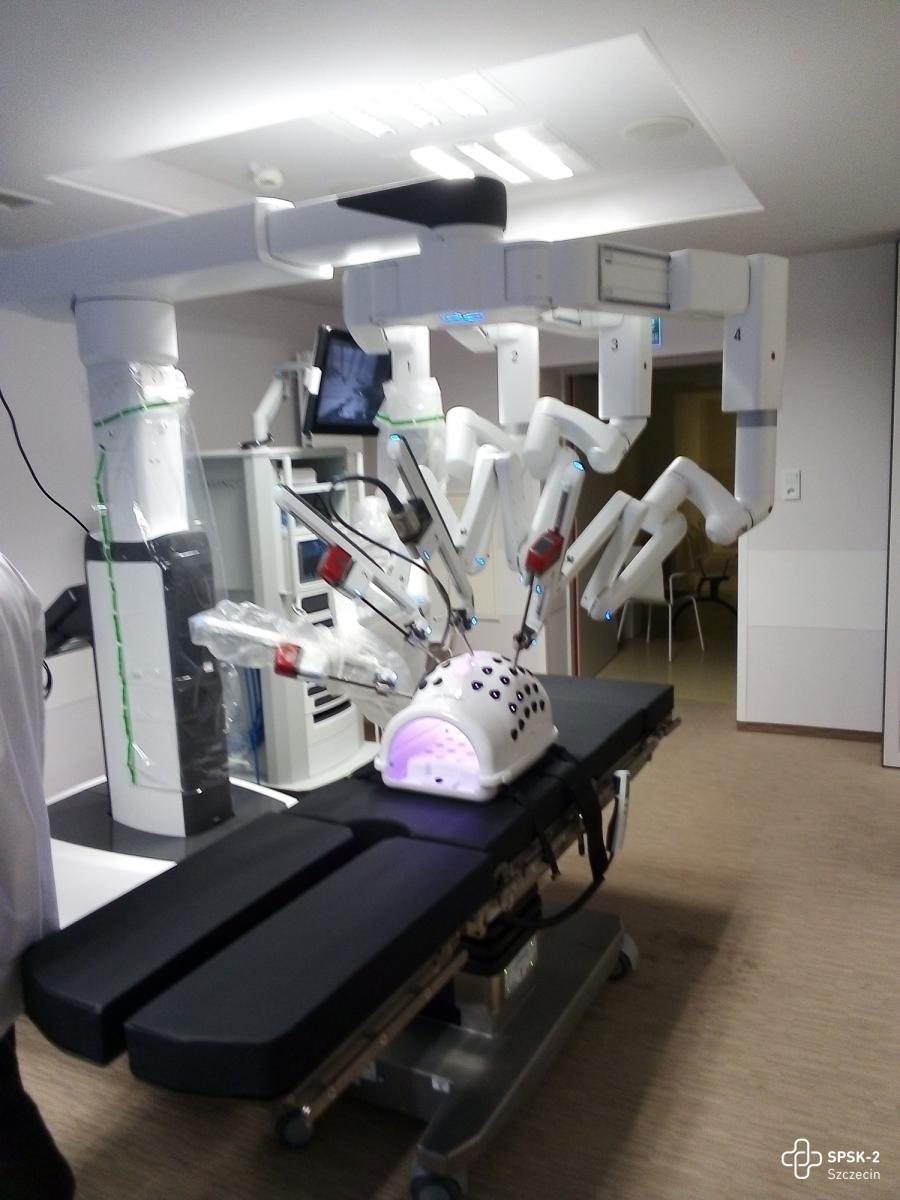

Fundusze przyznane dla naszego szpitala pozwolą podwyższyć poziom opieki onkologicznej naszych pacjentów. W ramach przyznanej kwoty planujemy m.in. zakup drugiego systemu chirurgii robotycznej, co pozwoli na podwojenie liczby operacji małoinwazyjnych. Nowością będą dwie konsole operacyjne, umożliwiające współpracę dwóch chirurgów w trakcie zabiegu. Szpital wzbogaci się również o aparaty RTG i USG, laser medyczny, robot cytostatyków, który trafi do szpitalnej apteki, ponad 100 łóżek szpitalnych, system mikroskopii wirtualnej, siedem stołów operacyjnych oraz dwa zestawy laparoskopowe. Na liście zakupowej znajduje się blisko 130 pozycji, obejmujących blisko 400 urządzeń, co znacząco poprawi jakość świadczonych usług i komfort pacjentów.

Wywiad z prof. Marcinem Słojewskim, lekarzem kierującym Kliniką Urologii I Onkologii Urologicznej USK-2 w Szczecinie na temat systemu robotycznego da Vinci

2023-12-28Link do wywiadu: www.facebook.com/TVPSzczecin

12.10-12.30 Operacje przy wsparciu systemu robotycznego da Vinci

12.10-12.30 Operacje przy wsparciu systemu robotycznego da Vinci